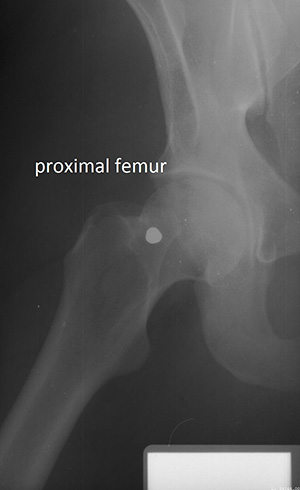

研究人员比较了20个人死前和死后的侧颅面(头骨的一侧)x光片,50个人的脊柱(脊柱)x光片,23个人的股骨近端(大腿)x光片。研究人员利用这些评估来为每个骨骼区域制定特定位置的标准。研究人员之所以关注这些骨骼区域,是因为它们是临床环境中x光照射最频繁的区域之一。

文摘:本研究的目的是评估在标准x线照片中可见的各种解剖特征的使用,并开发一套标准系统来评估一致性特征,以便通过x线照片比较作出积极的鉴别。研究中使用的x线片包括颅面(n = 41)、胸部(n = 100)和股骨近端(n = 49),这些x线片由北卡罗莱纳州首席法医办公室提供。根据一致性特征的数量对x线片进行评分,并使用分类决策树进行分析。分类树模型的准确性是利用接收者的工作特性来评估的。侧颅x线片需要两个或两个以上的一致性点,阳性鉴别的概率为97%。如果颈椎上存在一个以上的一致性特征,则有99%的概率正确识别。对于胸椎和腰椎,需要4个或更多的一致性特征才能有98%的正确识别概率。如果有1个或更多的股骨头和颈部一致性特征,正确识别的概率分别为94%和97%。本研究在3张标准的x线照片中确定了确认阳性识别所需的最小协调区域数目。